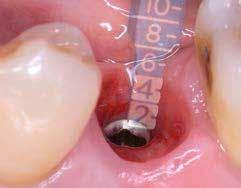

A behelyeztt implantátum primer stabilitását megfelelőnek ítéltük (kb. 40 Ncm) az azonnali terheléshez (9. kép).

Az extrakciót megelőző szituációs lenyomat alapján gyári, titán, ideiglenes abutment felhasználásával, a szék mellett készített, csavaros rögzítésű, azonnali akrilát ideiglenes koronával láttuk el, melyet 20 Ncm nyomatékkal rögzítettünk (10. kép). Az azonnali terhelés szabályainak megfelelően, az ideiglenes korona nem volt kontaktusban a szomszédos és az antagonista fogakkal.

6. kép: Implantátum-ágy preparáció. 7. a–b. képek: Implantátum behelyezés. 8. kép: A behelyezett implantátum. 10. a–b képek: Azonnali ideiglenes korona készítése. 9. kép: Megfelelő primer stabilitás.

10. c–d képek: A kész ideiglenes korona. 11. kép: A 6 hónapos kontroll felvétele.

12. kép: A 6 hónapos intraorális kontrollröntgen felvétele.

A 2020 januárjában elkezdett kezeléssorozat befejezését az év márciusában, hazánkba is begyűrűző Covid-19 pandémia késleltette, így kb. 6 hónap gyógyulás után láttunk hozzá az emergencia profil és a gingivális zenit ideiglenes koronával történő formázásához (11. és 12. kép). A 3 hetente végzett apró alakításokkal sikerült megfelelő ínyprofilt kialakítani, a „rózsaszín esztétika” a páciens számára is megfelelő volt. A bal felső nagymetsző fog meziális kompozit tömés cseréjét követően, individualizált nyitott kanalas lenyomati fejet készítettünk: az akrilát ideiglenes korona profilját átlátszó szilikonnal lemásoltuk, majd a körszimmetrikus gyári lenyomati fej és az ideiglenes korona kontúrja közötti hézagot folyékony kompozittal töltöttük ki (13. kép). Az így készített egyéni lenyomati fejjel vettünk lenyomatot a végleges, kerámialeplezésű cirkónium-dioxid vázas, átmenő csavaros rögzítésű koronához. (A fogtechnikai munkát Nébl Péter fogtechnikusmester készítette.), (14., 15., 16 és 17. képek).